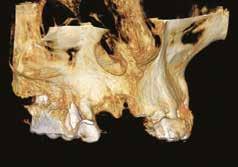

Eseguiti i rilievi diagnostici si propone in prima fase la estrazione del 12 e 11 dopo aver tagliato il ponte in bocca, mesialmente all’elemento 22, sostituendo provvisoriamente con protesi mobile gli elementi mancanti. Dopo le estrazioni e a guarigione dei tessuti avvenuta (foto 02), CBCT (foto 03) e rilievo dell’impronta ottica, si progetta l’inserimento di 2 impianti in Chirurgia guidata e contestuale GBR utilizzando sostituto osseo arricchito e inglobato in CGF, quello cioè che chiamasi Sticky Bone. Viene progettato in software di Chirurgia Guidata l’inserimento prima dei denti mancanti e poi dei 2 impianti in posizione ideale per la riabilitazione protesica. (fig. 04-05-06)

A progettazione implanto-protesica ultimata si disegna una dima chirugica che poi verrà stampata con Stampante 3D a tecnologia DLP. (fig. 07). L’intervento viene eseguito in anestesia locale con Articaina 1:200.000, si apre un lembo a tutto spessore e si posiziona la dima ad appoggio dentale, si inseriscono gli impianti programmati, si coprono alcune spire implantari esposte e si aumenta il volume osseo vestibolare con Sticky Bone. (fig. 08) A copertura della GBR si posiziona una membrana di CGF. Particolare attenzione viene posta nella sutura a più strati che ci dia contemporaneamente la certezza dell’immobilizzazione dell’innesto e della guarigione per prima intenzione della ferita. (fig. 09-10). Dopo circa 5 mesi si procede con la riapertura degli impianti (fig. 11) e dopo la guarigione dei tessuti si prende impronta ottica con Scan Bodies.